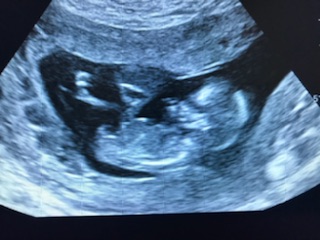

Well I had an unexpected scan today because we couldn't find hb on Doppler and unfortunately there was no hb on ultrasound . Wish it were wrong. I'm pretty heartbroken as we just heard it. Anyway just wondering if there are any Attachment 39531clues in these pics

Top pic shows a forked nub but not like girly forks I've seen, not to say that it isn't of course, just that I'm not familiar with them looking like that.